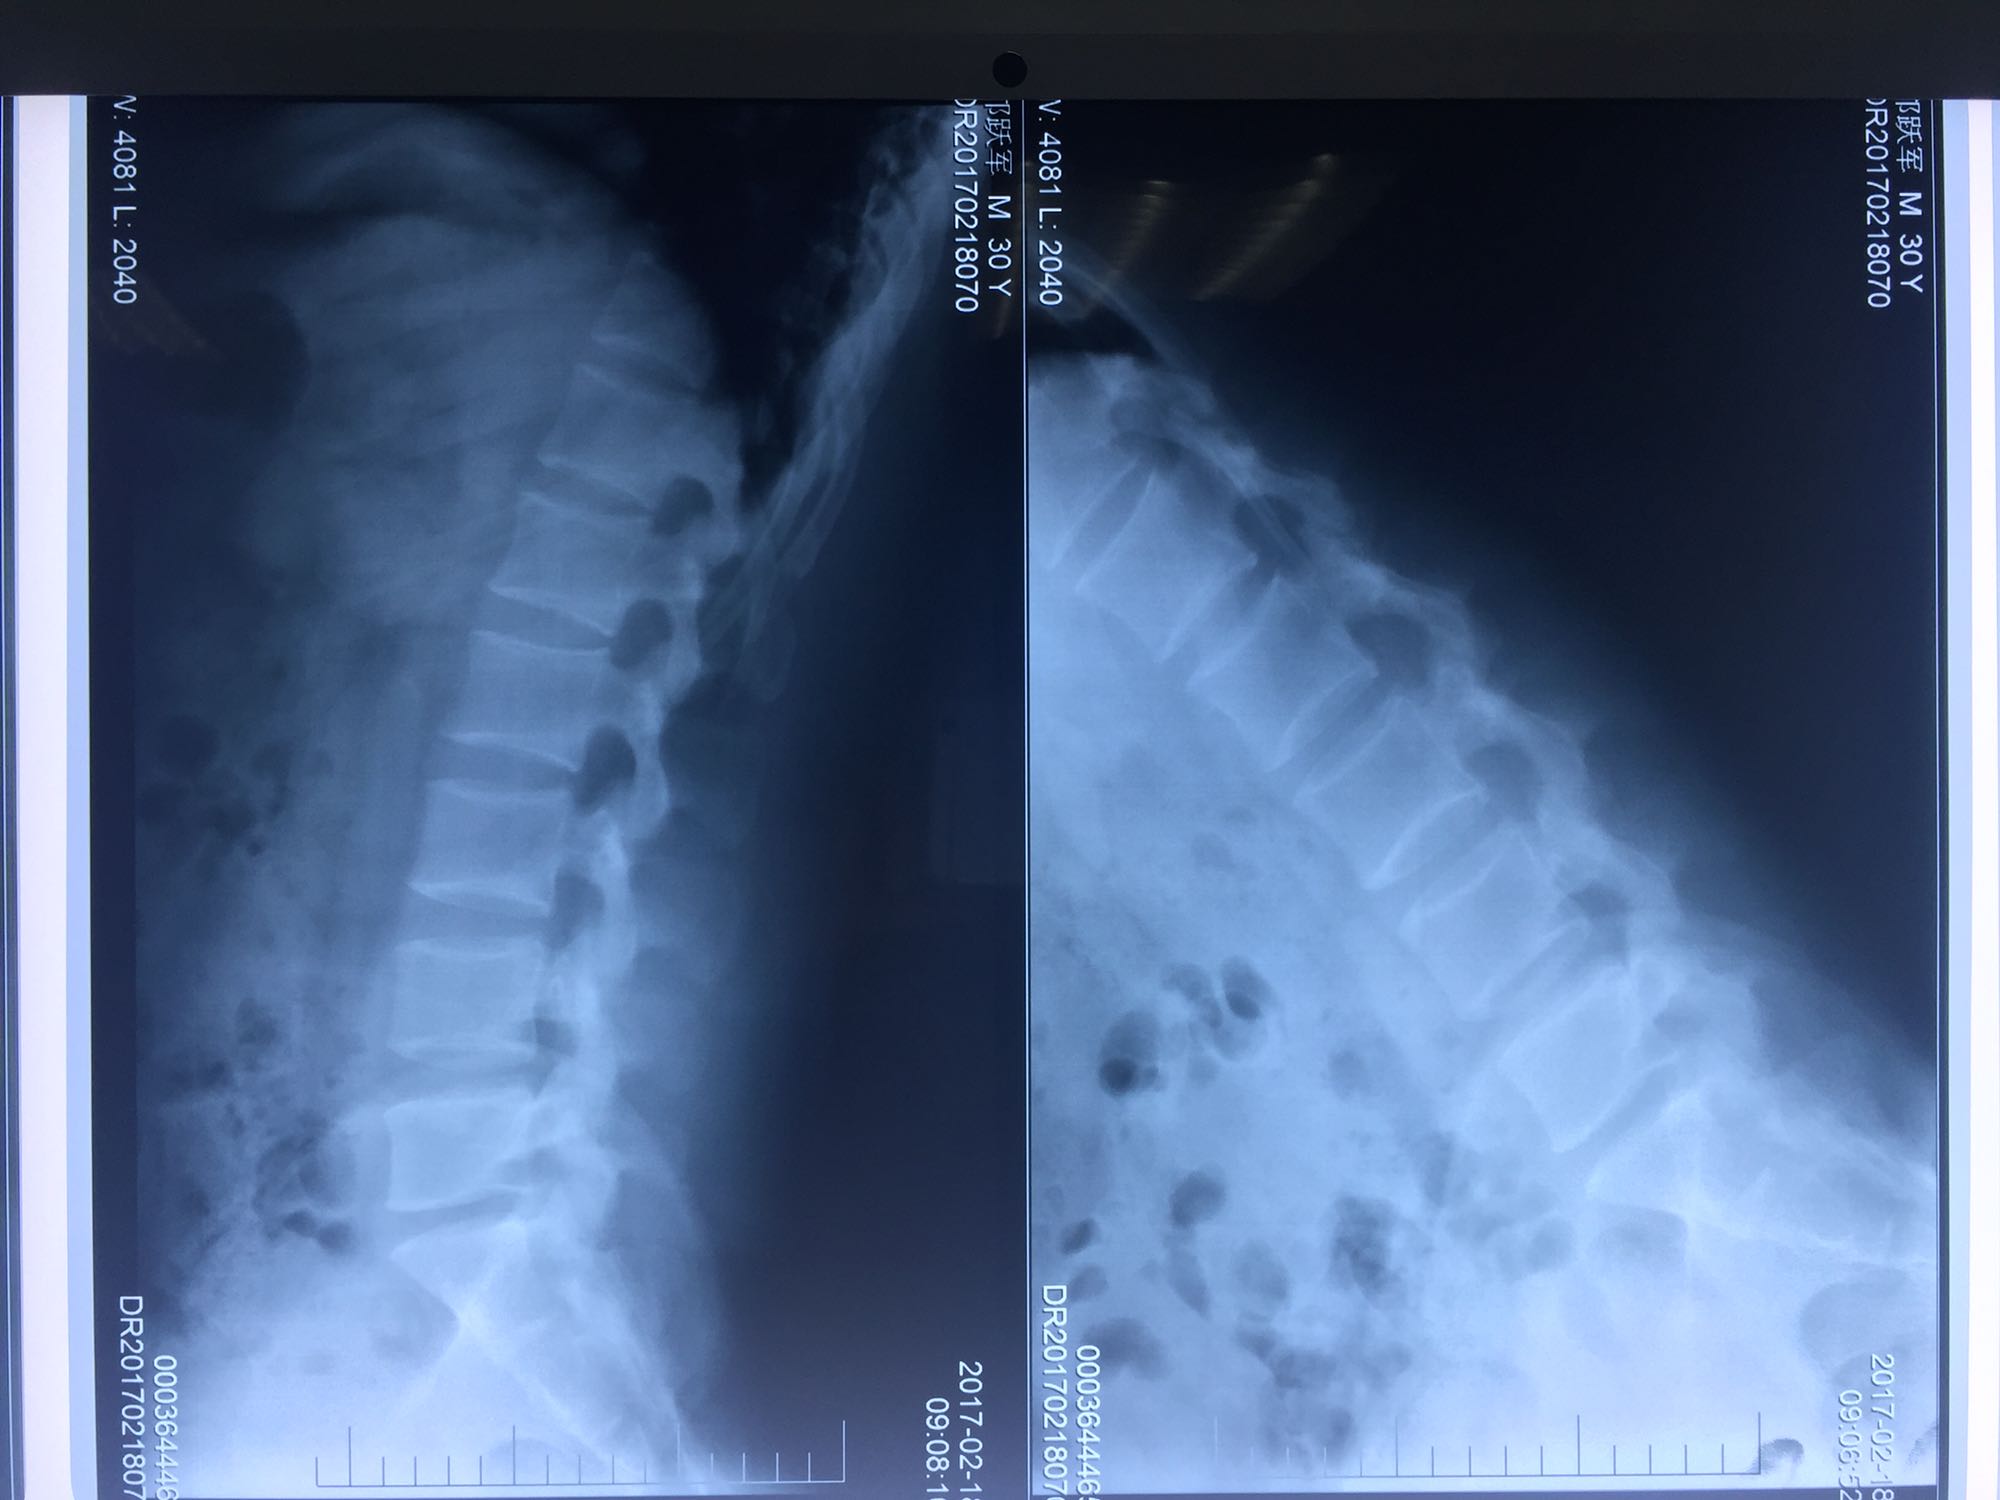

椎间孔镜下腰5骶1椎板间隙入路髓核摘除术

腰椎间盘脱出

邝X军,男性,30岁,因左下肢疼痛1天而入院。 1天前无明显诱因出现左下肢疼痛,程度较重,难以忍受,伴有行走困难。

腰骶部肌紧张,腰5骶1棘间及左侧椎旁有压痛及放散痛,左侧坐骨神经出孔处有压痛及放散痛,左侧足背外侧及足底部皮肤感觉麻木,左侧直腿抬高试验阳性(30度)。

诊断:腰5骶1椎间盘突出症 治疗方案:椎间孔镜下经椎板间入路髓核摘除术